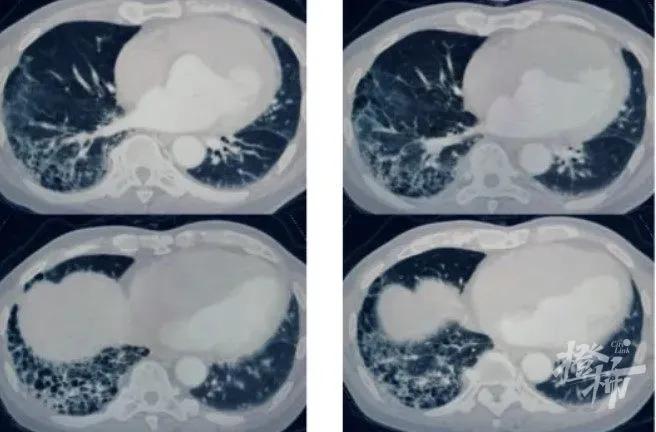

77歲的王大伯比同齡人看著年輕許多,他是個(gè)很注重健康的人,日常進(jìn)行一些力量訓(xùn)練維持好身材。前不久,王大伯突然開(kāi)始咳血,一開(kāi)始以為只是支氣管炎犯了,萬(wàn)萬(wàn)沒(méi)想到的是,竟然是自己害了自己。這天,王大伯來(lái)到杭州市第一人民醫(yī)院呼吸內(nèi)科門診,想要一探究竟。接診的呼吸內(nèi)科主任醫(yī)師沈凌卻感到這事略微蹊蹺。因?yàn)橥醮蟛挥猩倭靠妊Y狀,除此以外,他沒(méi)有咳嗽、咳痰的情況,整個(gè)人的精神狀態(tài)也還好。這個(gè)情況和大多數(shù)支氣管炎病人并不完全相符,難道還有其他原因?沈凌醫(yī)生立即為病人安排了肺部CT檢查,在查看影像資料時(shí),他驚訝地發(fā)現(xiàn),王大伯肺部已經(jīng)出現(xiàn)明顯的肺纖維化特征,更為嚴(yán)重的是,局部已經(jīng)形成了蜂窩狀的病變形態(tài)。